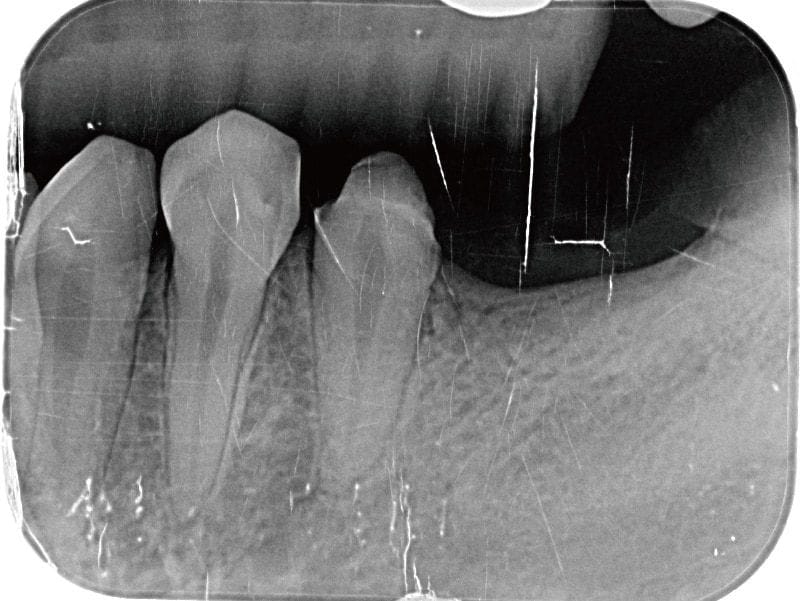

圖示:左下後牙區的假牙和臼齒殘根 圖示:左下後牙區X光片,箭頭處為假牙與臼齒殘根

Miss Sung 在牙周方面,雖然本身沒有什麼主觀的症狀,但還是有部分區域有比較深的牙周囊袋,與初期的齒槽骨流失。特別在左上後牙區也是有一組密合度已經不甚理想的假牙,容易造成牙菌斑或牙結石的殘留,屬於牙周病風險比較高的區域。

圖示:假牙拆除前的X光片 圖示:假牙拆除前的X光片